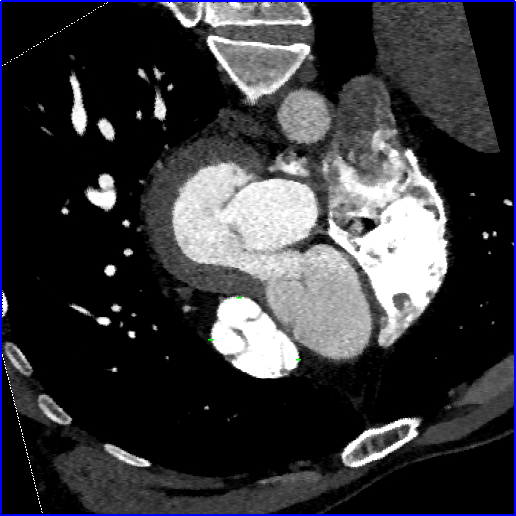

术前心脏CT评估

法洛四联症术后改变,室间隔、右室流出道前壁及肺动脉瓣水平多发片状钙化影。主肺动脉-右室流出道成角,肺动脉瓣形态欠规则。主肺动脉、左侧肺动脉干扩张,左肺动脉干直径约26mm;右位主动脉弓。右心房、右心室增大,右心室肌层增厚,心腔内未见明确充盈缺损影。冠状动脉左冠优势型,左主干起始段位于主动脉窦-主肺动脉之间,管腔未见显著狭窄。右心室流出道内径约36mm;主肺动脉瓣环内径约28mm;主肺动脉内径约38mm;主肺动脉发分叉处至右心室流出道长度约55mm。

术前增强CT图像显示肺动脉瓣结构损害